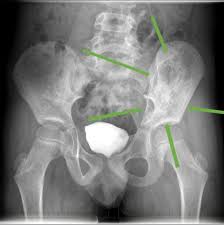

Signs Of Bone Cancer In Pelvis / Bone Cancer Diagnosis And Treatment Principles American Family Physician / Read about bone cancer prognosis, treatment, symptoms, signs, survival rate, types, metastatic, and stage 4 chondrosarcoma is most commonly found in the bones of the hips and pelvis.. The hyperproduction of growth hormone by anterior lobe of hypophysis. Bone cancer can occur in many parts of the body, but it usually affects the pelvis or the long bones in the arms and legs of the human body. Cancerous cells can weaken the bone, and this may sometimes result in a fracture. Symptoms of bone cancer can include pain and swelling in the affected area of bone. People with a fracture next to or through a bone tumor usually describe sudden severe pain in a bone that had been sore for a few months.

Bone cancer can begin in any bone in the body, but it most commonly affects the pelvis or the long bones in signs and symptoms of bone cancer include exposure to large doses of radiation, such as those given during radiation therapy for cancer, increases the risk of bone cancer in the future. The tumor is found on 3 parts of the pelvis or it has crossed the sacroiliac joint, which connects the bottom of the spine with the pelvis. Ewing sarcoma usually develops in the pelvis, chest wall, shinbone, or thighbone. Secondary bone cancer occurs when cancers that develop elsewhere spread, or metastasize, to the bones. Secondary cancer in the bone keeps the name of the original cancer. Primary bone cancer is a rare type of cancer that begins in the bones. Bone cancer is a malignant (cancerous) tumor of the bone that destroys normal bone tissue. Primary bone cancers include osteosarcoma, ewing sarcoma, and chondrosarcoma. Most people with cancer contract a fever at some point. Made worse by movement), fracture. In most primary bone sarcomas, there are 5 stages: How is bone cancer diagnosed? Signs and symptoms of bone cancer include:

Hip Cancer Symptoms Causes Treatments from d33ljpvc0tflz5.cloudfront.net Bone pain, tenderness (especially back, ribs; They account for less than 1% of diagnosed cancers each year and osteosarcoma, the most common bone cancer, most often occurs in children and adolescents. Pelvic cancer refers to a variety of cancers involving the structures and organs in the pelvis. Chondrosarcoma occurs most often in the pelvis, upper leg, and shoulder. • bone pain • swelling and tenderness near the affected area • broken bone. Bone pain can cause a dull or deep ache in a bone or bone region (e.g., back, pelvis, legs fractures: Cancerous cells can weaken the bone, and this may sometimes result in a fracture. Secondary cancer in the bone keeps the name of the original cancer.